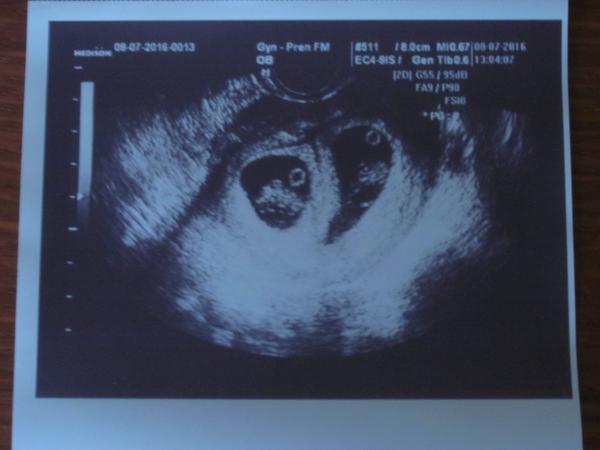

Jinak já jsem po 1. IVF, už 7. den od ET jsem měla //, minulý týden na UTZ potvrzeny dvě bublinky, dneska jsem 5tt+4 a už se do ničeho nevejdu - mám dojem, že s dvojčátkama bude všechno mnohem intenzivnější a rychlejší 😀

@adusee Já byla na první kontrole až 9 tt+1, a bylo krásně slyšet i srdíčko, ale doktor nepoznal nic. Akorát říkal, že už to je dost velké, ale asi tím myslel, že mu tam chodí maminky hned v 6. týdnech. Já jsem neměla kam spěchat. A pak jsem ve 13. týdnu začala krvácet, a můj doktor měl dovolenou, tak jsem jela do nemocnice a doktor mi říkal, že tam jsou 2. K mému doktorovi jsem pak šla za 10 dní na objednaný termín kontroly a divil se. Oni byli schovaní za sebou.